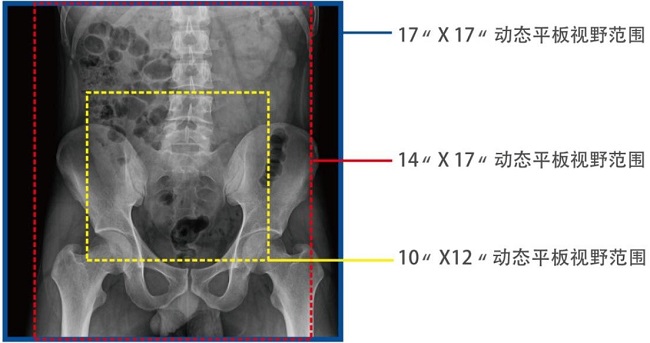

17*17英寸的超高清像素動態(tài)平板探測器,更大的視野范圍,能對胸部腹部等部位實現(xiàn)大范圍全覆蓋,動靜態(tài)之間無感切換。透視檢查無須對患者重新定位便可觀察到足夠大的人體器官組織,避免漏診誤診。

大尺寸動態(tài)平板技術(shù),覆蓋檢查面積范圍廣,輕松實現(xiàn)胃十二指腸等大面積造影,無需移動即可觀看整個動態(tài)過程,避免噪點對圖像的影響。